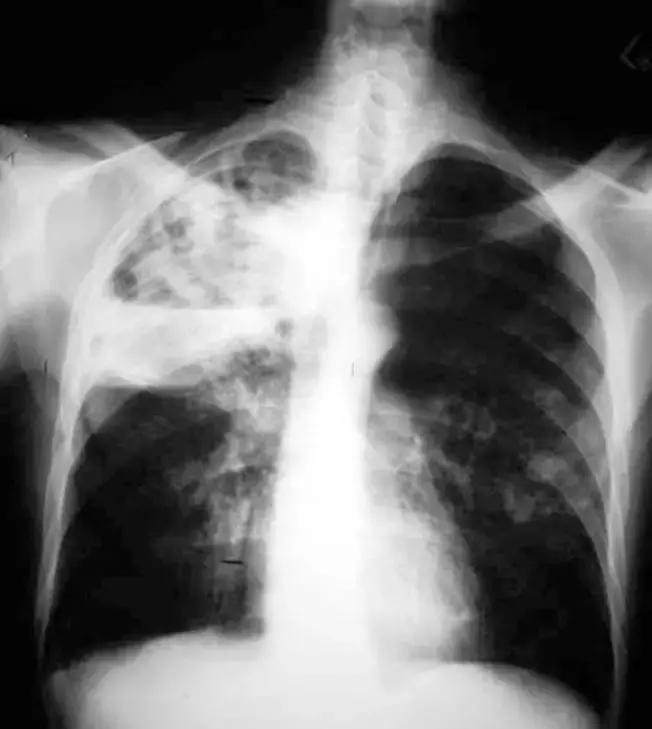

外院(6.27)胸部CT提示双肺感染,先后予「阿奇霉素、头孢哌酮/舒巴坦」抗感染等治疗,患者胸痛、呼吸困难无缓解。

胸部CT(6月27日)提示双肺多发实变、斑片影、结节影。

*影像学显著进展

7月3日:

7月10日:

7月27日胸部CT